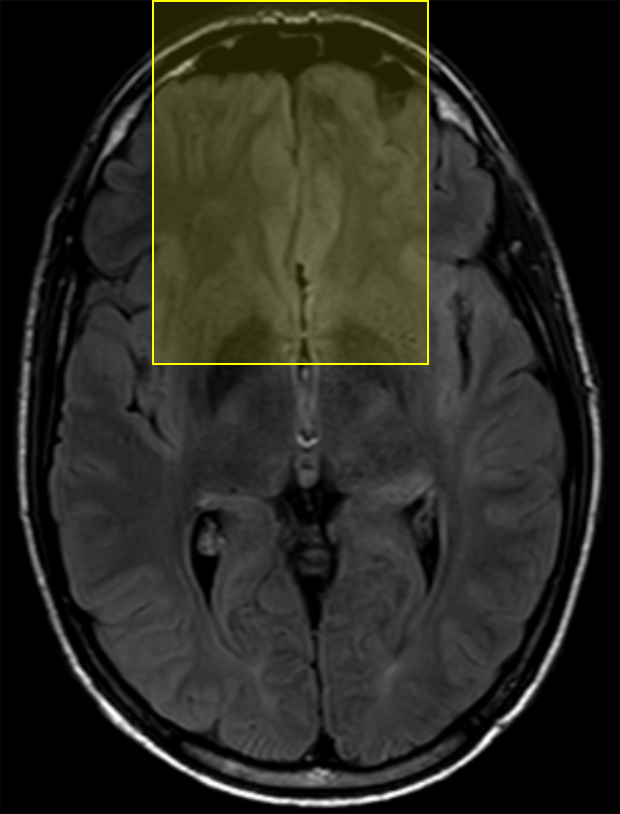

We performed pairwise comparison between two scans of a 32-year-old basketball player, diagnosed with mild occipital traumatic brain injury and frontal hemorrhage due to contrecoup impact, acquired one week and 6 months post-injury. The hemorrhagic lesion at the frontal right hemisphere of the player is no longer visible in the FLAIR image acquired 6 months after injury (Fig. 2a). Local differences between corresponding, longitudinal FA- and MD-FFDD profiles of the FMT (chosen due to its proximity to the lesion area) are shown in Fig. 2d. Figs. 2b-c present color-coded FMT to visually demonstrate these differences. Results show significant longitudinal variability at the right hemisphere part of the tract, corresponding to the lesion area, and relatively minor differences along the rest of the tract. These results should be considered as a proof of concept, validating the FFDD analysis results for the detection and localization of mTBI-related variabilities between fiber bundles.

| 6 MONTHS | ![]() |

![]() |

MD-FFDD |

| (a) FLAIR | (b) FA-FFDD | (c) MD-FFDD | (d) Local Differences |